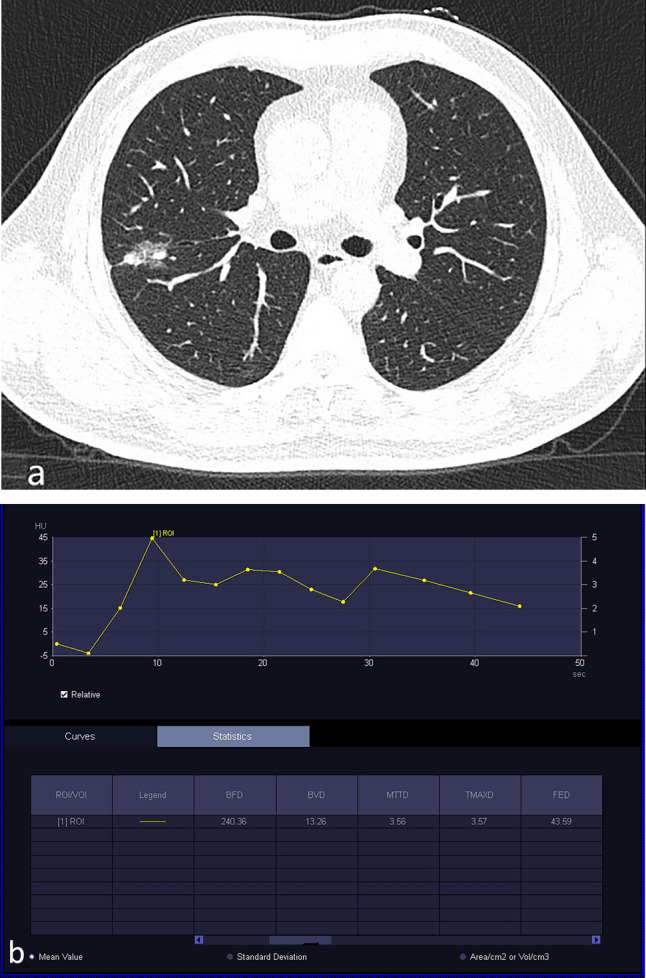

Figure 3.

Inflammatory GGO nodules. A 56-year-old woman patient presented with cough and sputum for 3 weeks. (a) Unenhanced CT on April 16, 2023, showed a part-solid nodule in the lower lobe of the right lung. (b) Based on the TDC of CT perfusion of the nodule on April 17, 2023, the curve shows a slowly rise pattern, followed by a plateau, and slowly decreasing pattern. (c) Based on the follow-up CT on May 19, 2023, the density of the nodule was decreased. (d) Based on the follow-up CT on December 6, 2023, the nodule in the lower lobe of the right lung have disappeared.